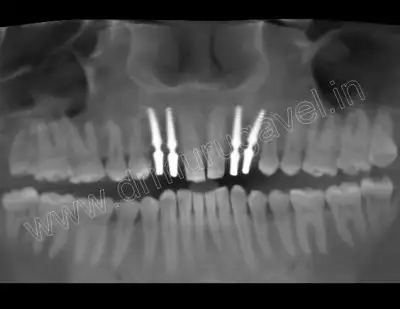

post implant x-ray

After implant placement

- Basal implant placed in extraction socket. 2 implants in 12,13 region and 2 implants in 22 and 23 region.